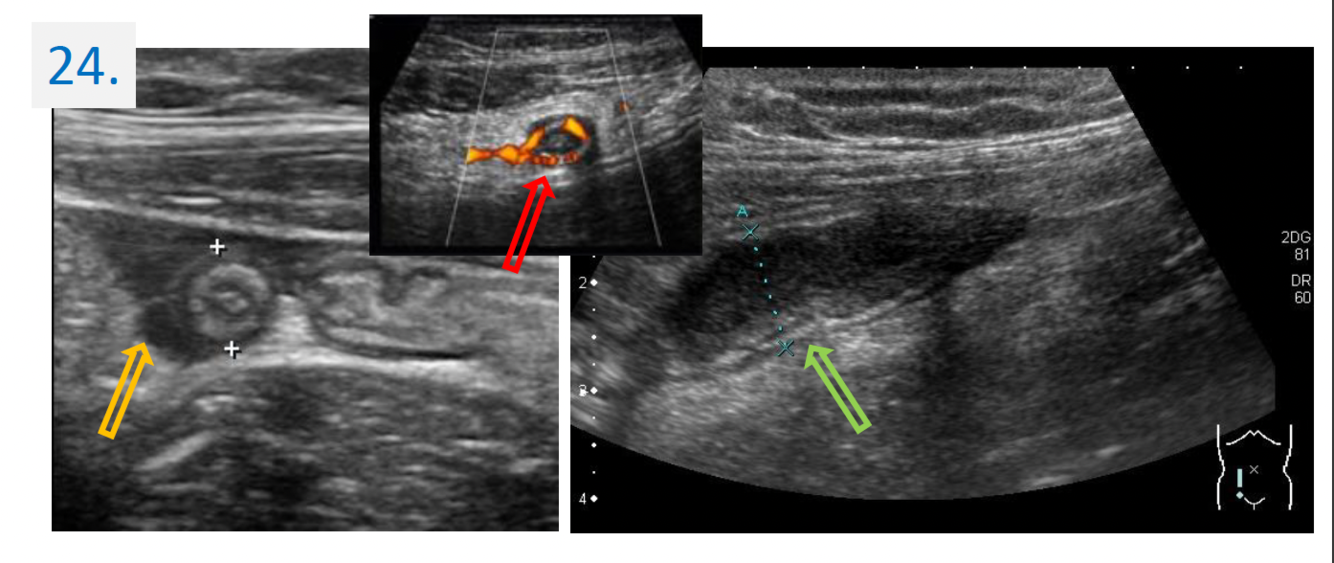

24

Diagnosis:

Acute appendicitis